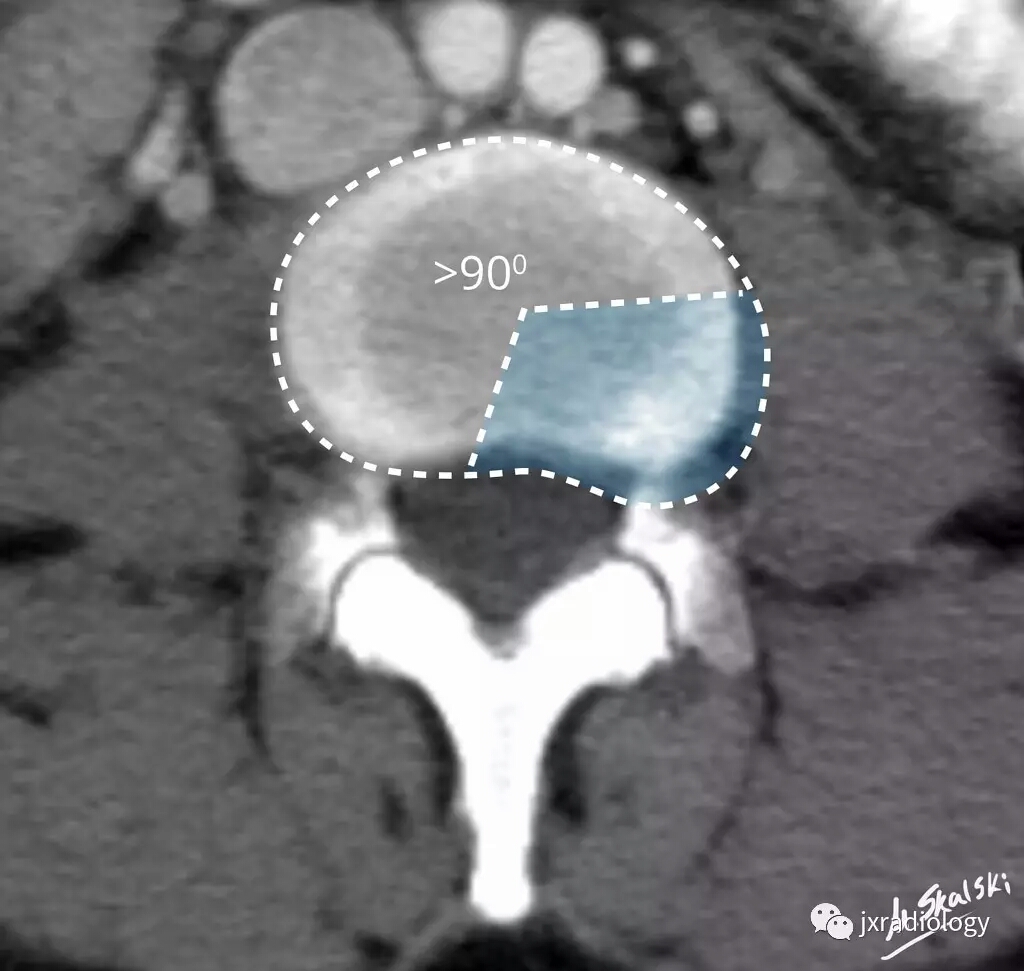

三、椎间盘突出(Disc protrusion)

椎间盘突出物小于椎间盘 25%(90度);而且,任何平面,突出物最大测量值均低于移位椎间盘来源的基底部。